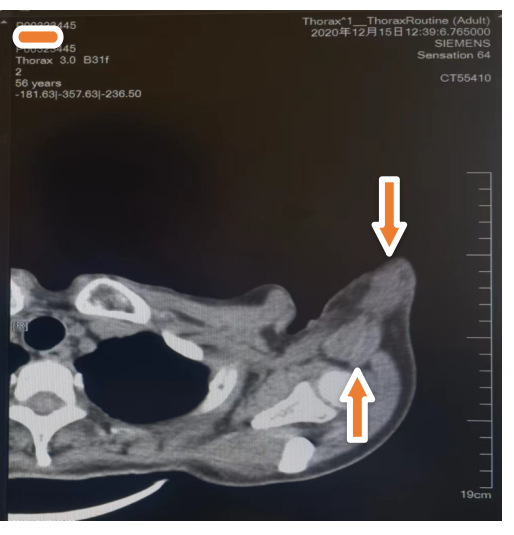

治疗5个月后 2020年12月15日